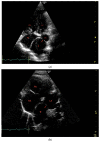

A five-month-old, 3.8 kg intact male Maine coon cat presented for dyspnea characterized by increased respiratory effort in addition to open-mouth breathing. Thoracic radiographs showed pectus excavatum, enlarged cardiac silhouette, and generalized interstitial patterns. Echocardiography revealed normal left atrial (LA) and left ventricular dimensions. A large tubular structure, suspected to be a distended pulmonary vein (PV), was identified as draining into the LA. Severe eccentric and concentric right ventricular hypertrophy and paradoxical septal motion were noted. Based on Doppler echocardiography, both pulmonary venous and pulmonary artery pressure was severely elevated. Clinical, radiographic, and echocardiographic abnormalities were hypothesized to result from pulmonary vein stenosis (PVS), causing severely elevated pulmonary venous pressures and resulting in clinical signs of left-sided congestive heart failure (L-CHF) and severe post-capillary pulmonary hypertension (Pc-PH). The prognosis for good quality of life was assessed as poor, and the owner elected euthanasia. Necropsy confirmed the presence of PVS with severe dilation of the PVs draining all but the left cranial lung lobe. All lung lobes except the left cranial lobe had increased tissue density and a mottled cut surface. This case report shows that, in rare cases, both L-CHF and Pc-PH may be present without LA enlargement. To the authors' knowledge, this is the first report on PVS in veterinary medicine.